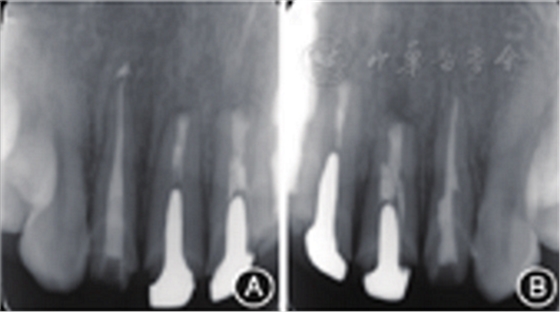

图8 术后3个月复查患者根尖X线片 A:根尖病变明显缩小;B:根尖病变明显缩小